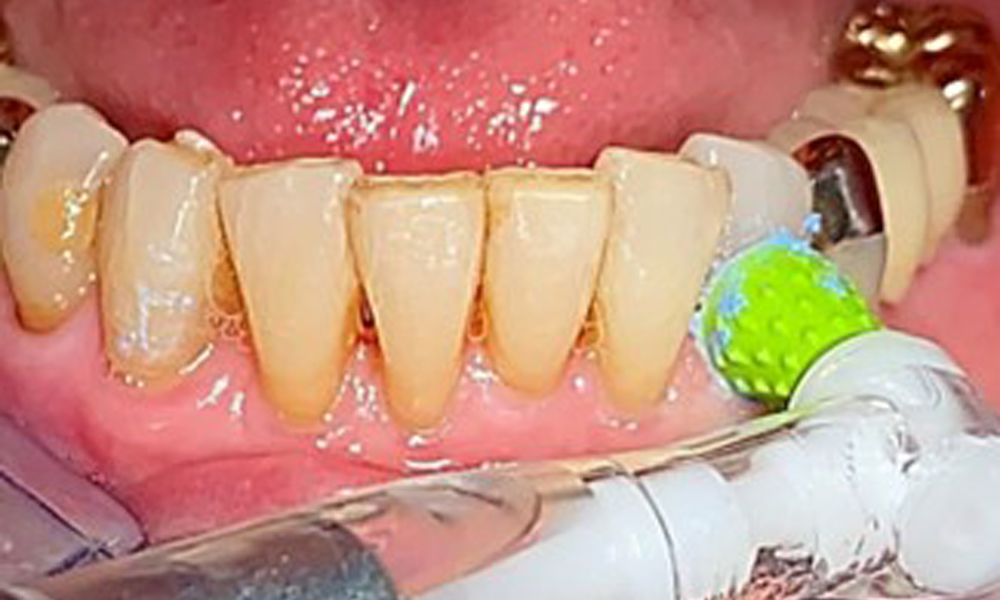

A single-tufted brush is specifically recommended for the telescopic prostheses (Fig. 8) and the patient should be advised on the appropriate interdental brush size (Fig. 9). The patient has been implementing these recommendations for intraoral hygiene at home for many years and was encouraged to continue during the professional preventive dental appointment.

Illustration of a single-tufted brush for home care of the implants and telescopic prostheses.

Fig. 8: Illustration of a single-tufted brush for home care of the implants and telescopic prostheses.

Interdental cleaning with brushes (Fig. 9) or dental floss is just as important as cleaning the tongue.